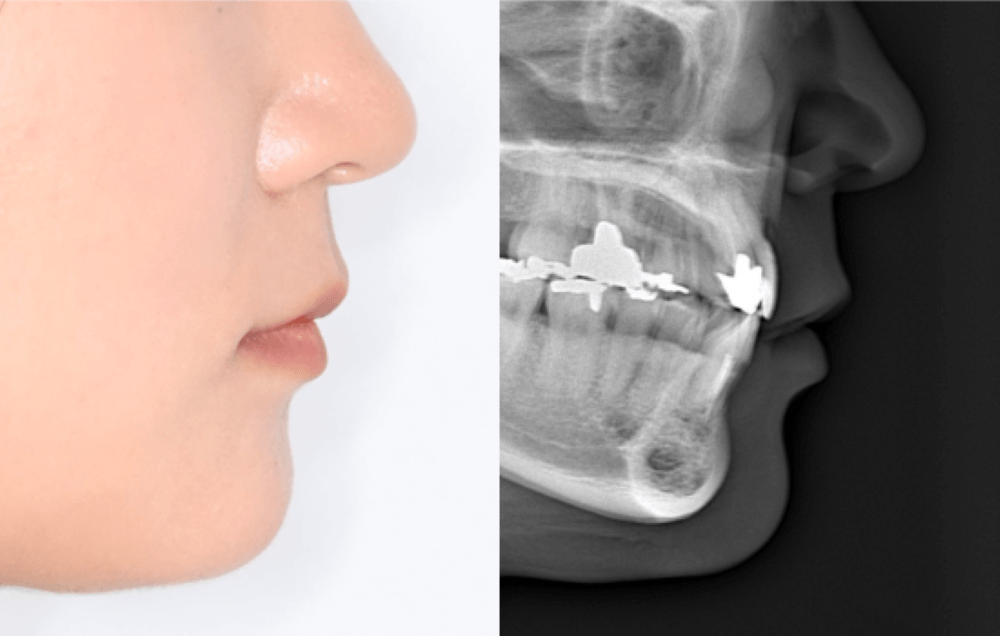

今回ご紹介するのは、「前歯と口元が出ていて、横顔が気になる」とご相談いただいた患者様の症例です。表側ワイヤー矯正と歯科矯正用アンカースクリューを併用して治療しました。 実際の治療前写真をもとに、どのように改善したのかをご […]